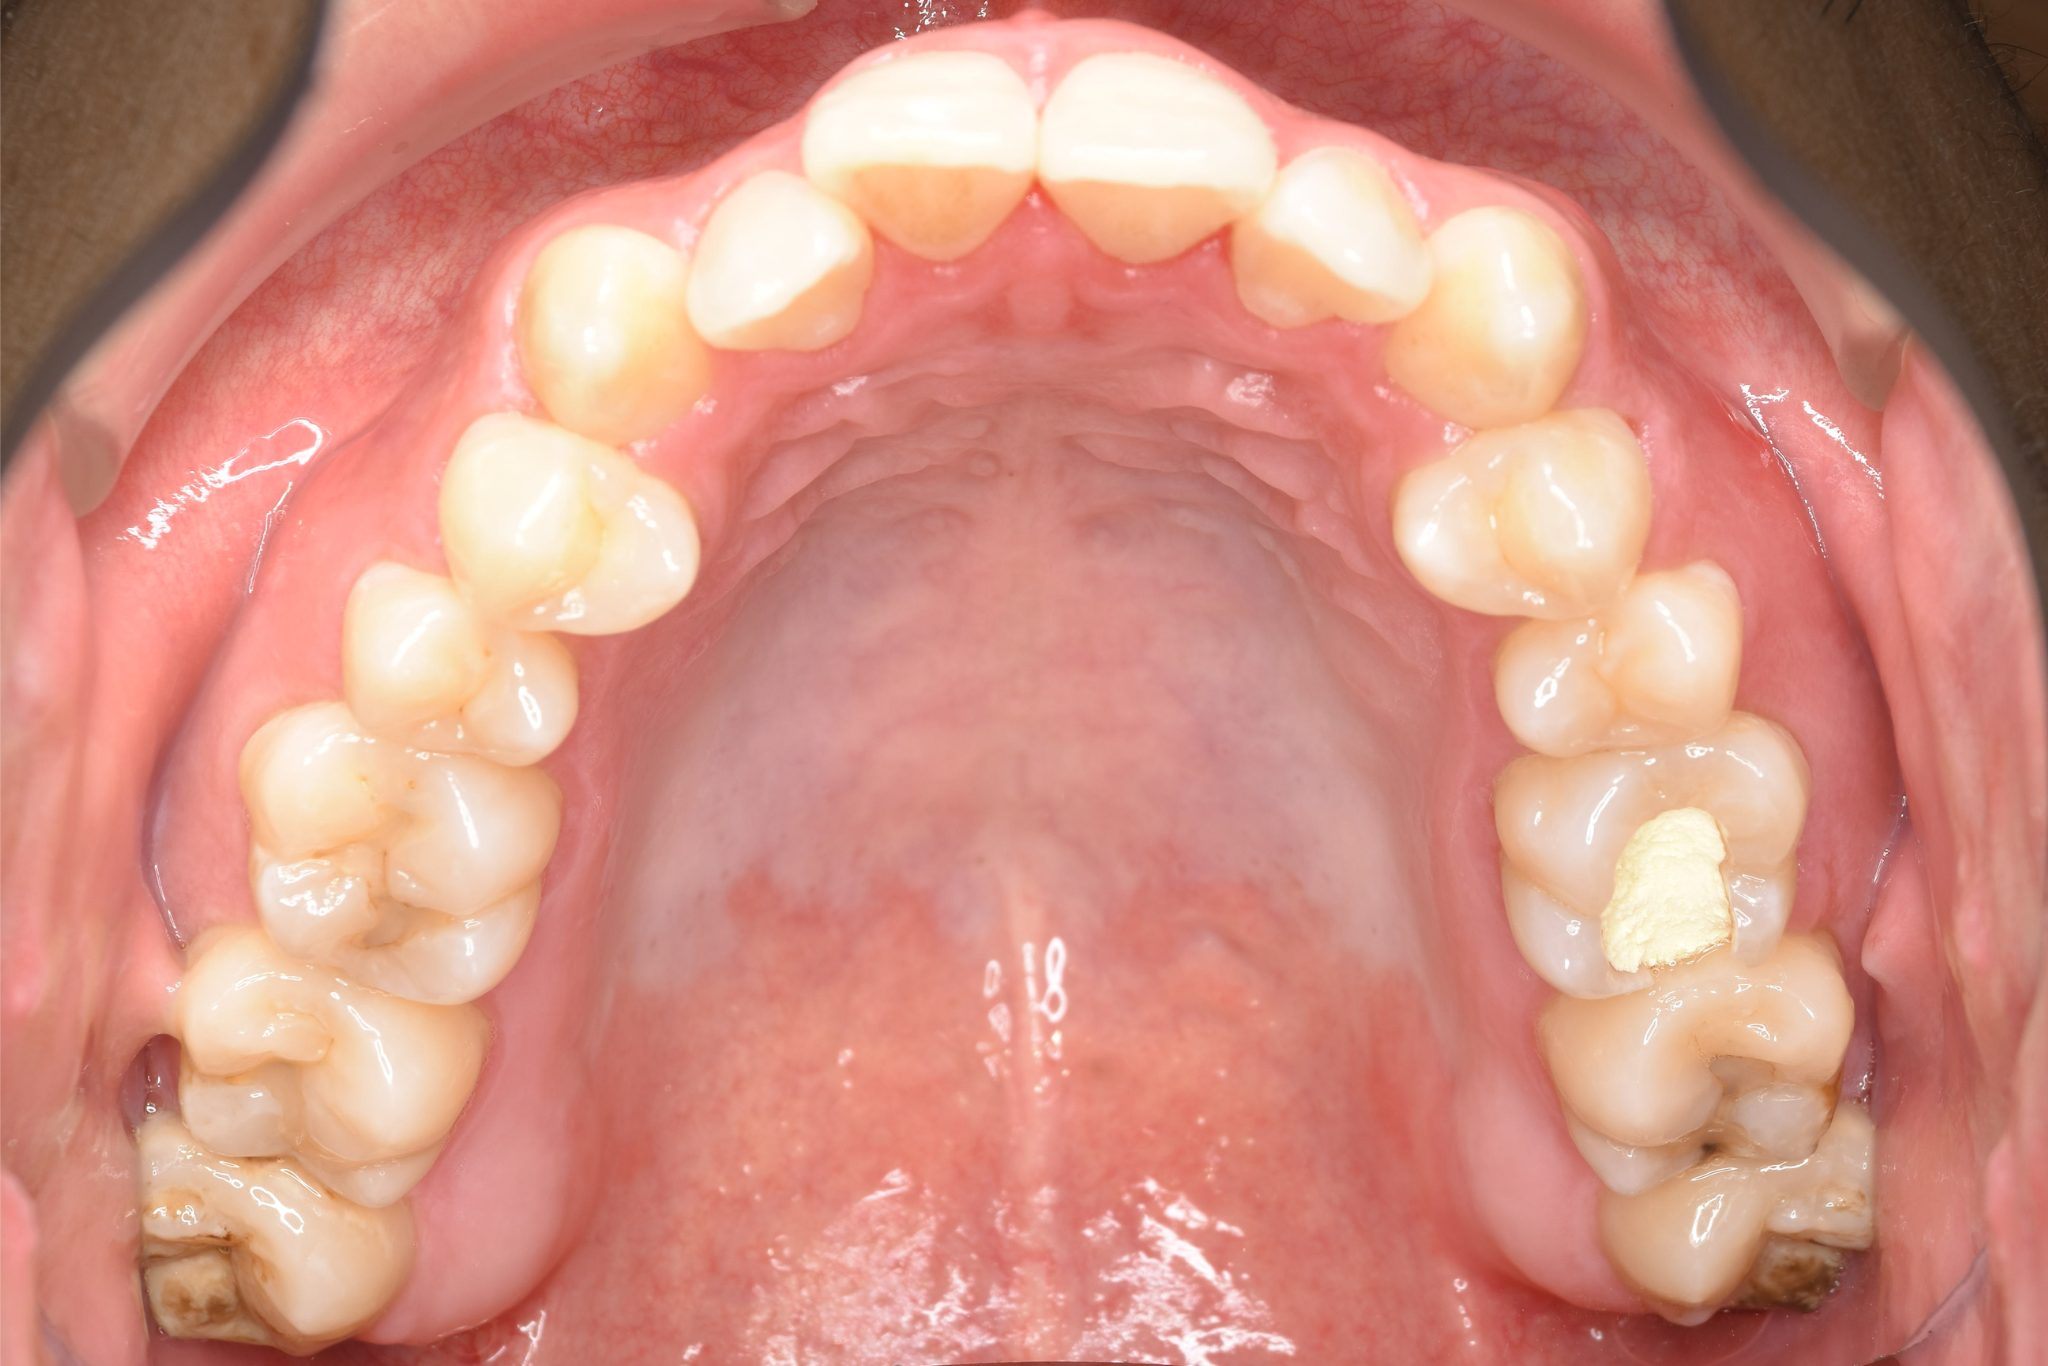

ビフォー

ワイヤー矯正治療|症例_495

主訴 受け口|かみ合わせ|面長

施術内容 MSEと下顎リンガルアーチを用いて上下顎骨を拡大した。

その後マルチブラケット装置とミニインプラントを用いて

非抜歯で歯牙を配列し、良好な咬合を獲得した。